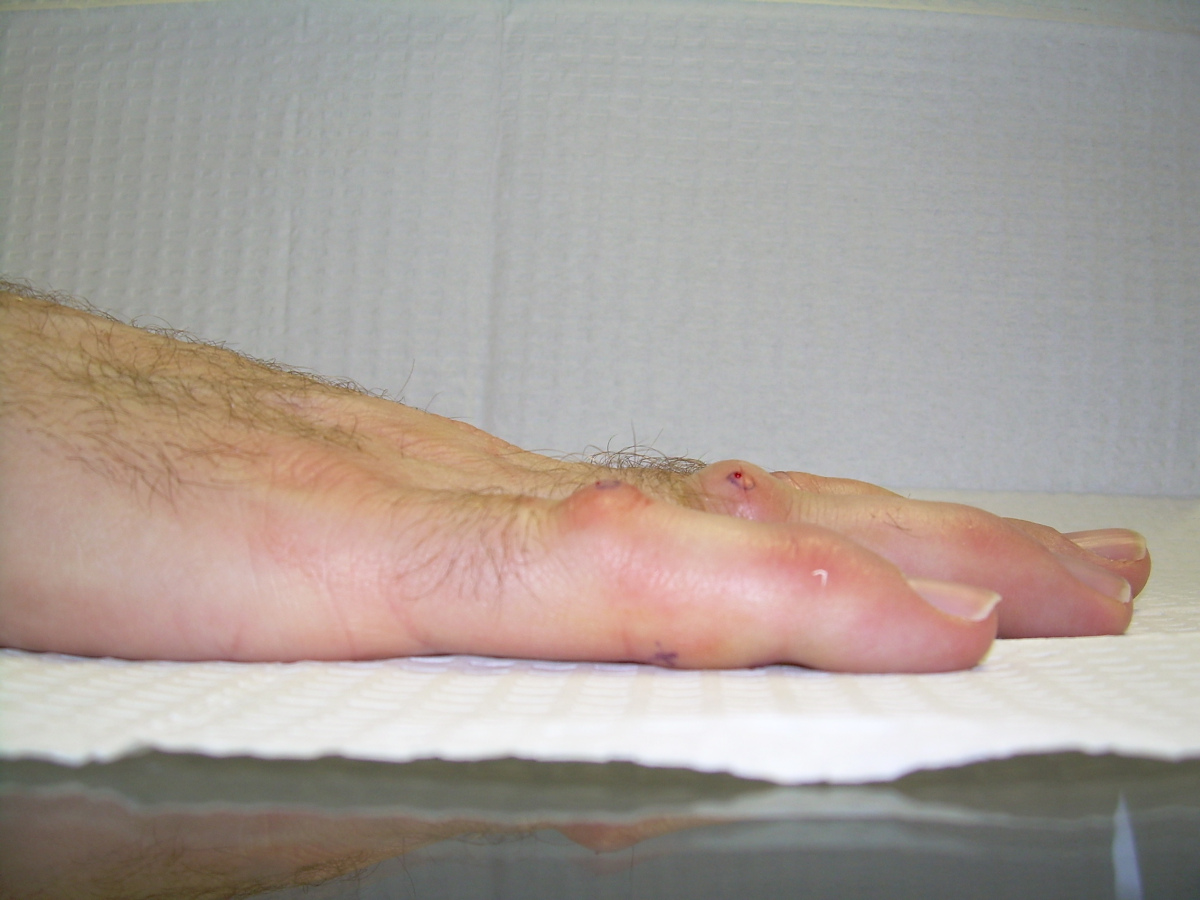

57 year old right handed man with a 22 year

history of Dupuytren disease affecting his

left small finger.

Highslide Highslide

Planning of portals (dots) and nodule steroid

injection sites (circles).

Radiograph of affected finger, 90° contracture.

End of Procedure. Minimal improvement, but the

joint felt rubbery to passive stretch, and so he

was treated with a night time static extension

splint. He had progressive improvement.